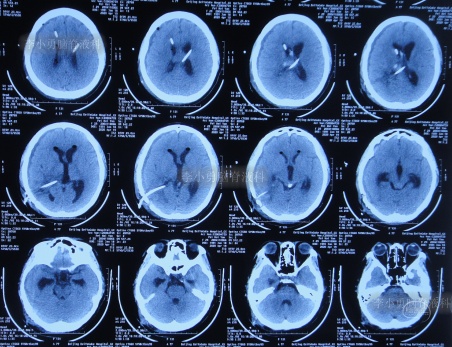

入院后4天即2020年4月15日,拔除了原3根分流管+两侧脑室外引流术(图-15)。

图-15:2020年4月15日头颅CT

图-16:2020年4月16日头颅CT

图-19:2020年4月19日头颅CT

入院治疗11天即2020年4月22日, 查头颅CT示脑室缩小,出血消失(图-20),头晕呕吐消失。

图-20:2020年4月22日头颅CT

入院治疗18天即2020年4月29日,进行了脑室腹壁外引流术,头颅CT示脑室缩小,脑室内仅有1根管(图-21)。

图-21:2020年4月29日头颅CT